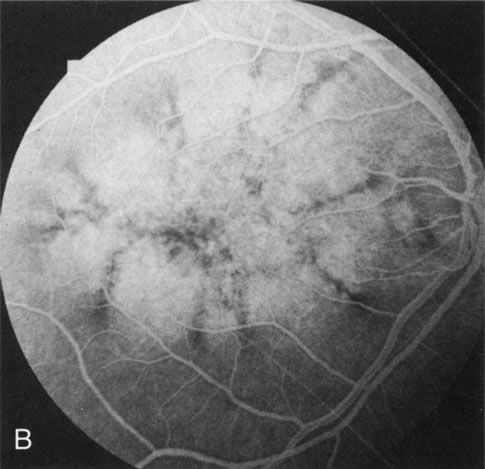

The fundus abnormalities in pigment pattern dystrophies may be subtle, especially when the pigmentary changes are orange and yellow in color. However, FA is most dramatic in highlighting these abnormalities. Thus, FA will confirm, and in some circumstances provide, the diagnosis (Fig. 11AE). Although there is no histopathologic confirmation, the fundus and angiogram suggest that an abnormal deposition of lipofuscin in the RPE is responsible for the clinical picture.

Fig. 11. Pigment pattern dystrophies. Subtle changes of the fundus in this family member with a pattern dystrophy (A) are highlighted on angiography (B). Equally dramatic is the fluorescein angiography of this young woman who presented with poor vision in association with a retinal hemorrhage (C). The angiogram reveals a bilateral, symmetric reticular pattern of the posterior pole (D, E).